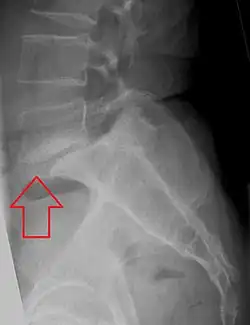

| X-ray of the lateral lumbar spine with a grade III anterolisthesis at the L5-S1 level | |

Spondylolisthesis refers to a condition in which one spinal vertebra slips out of place compared to another.[1] While some medical dictionaries define spondylolisthesis specifically as the forward or anterior displacement of a vertebra over the vertebra inferior to it (or the sacrum),[2][3] it is often defined in medical textbooks as displacement in any direction.[4][5]

Spondylolisthesis is graded based upon the degree of slippage of one vertebral body relative to the subsequent adjacent vertebral body.[6] Spondylolisthesis is classified as one of the six major etiologies: degenerative, traumatic, dysplastic, isthmic, pathologic, or post-surgical.[7] Spondylolisthesis most commonly occurs in the lumbar spine, primarily at the L5-S1 level, with the L5 vertebral body anteriorly translating over the S1 vertebral body.[7]

Classification by degree of the slippage, as measured as percentage of the width of the vertebral body:[17] Grade I spondylolisthesis accounts for approximately 75% of all cases.[7]

- Grade I: 0–25%

- Grade II: 25–50%

- Grade III: 50–75%

- Grade IV: 75–100%

- Grade V: greater than 100%